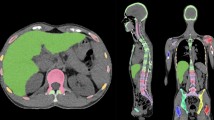

From the 113 FL patients identified from our database, 66 patients were ultimately included. Twenty-one patients were excluded because of missing BMB and 26 because of missing baseline 18FDG PET/CT. Fifty-nine patients were scanned on the Biograph TrueV Pet system, and seven were scanned on the Vereos PET system. There were 36 bone-NEGATIVE patients (54.5%) and 30 bone-POSITIVE patients (45.5%). Among the bone-POSITIVE patients, there were four BMB −/PETVISU + patients (13.3%), 14 BMB +/PETVISU− patients (46.7%) and 12 BMB +/PETVISU + patients (40.0%). Focusing on BMB −/PETVISU + patients, hypermetabolic lesions were located towards the axial skeleton and not in the appendicular skeleton, explaining the negativity of the BMB. Representative examples of each case are shown in Fig. 1.

For textural analysis, the skeleton volumes of interest (VOIs) from the C3 vertebra to the upper third of femurs were automatically extracted from CT images for each examination (Supplemental Fig. 1).